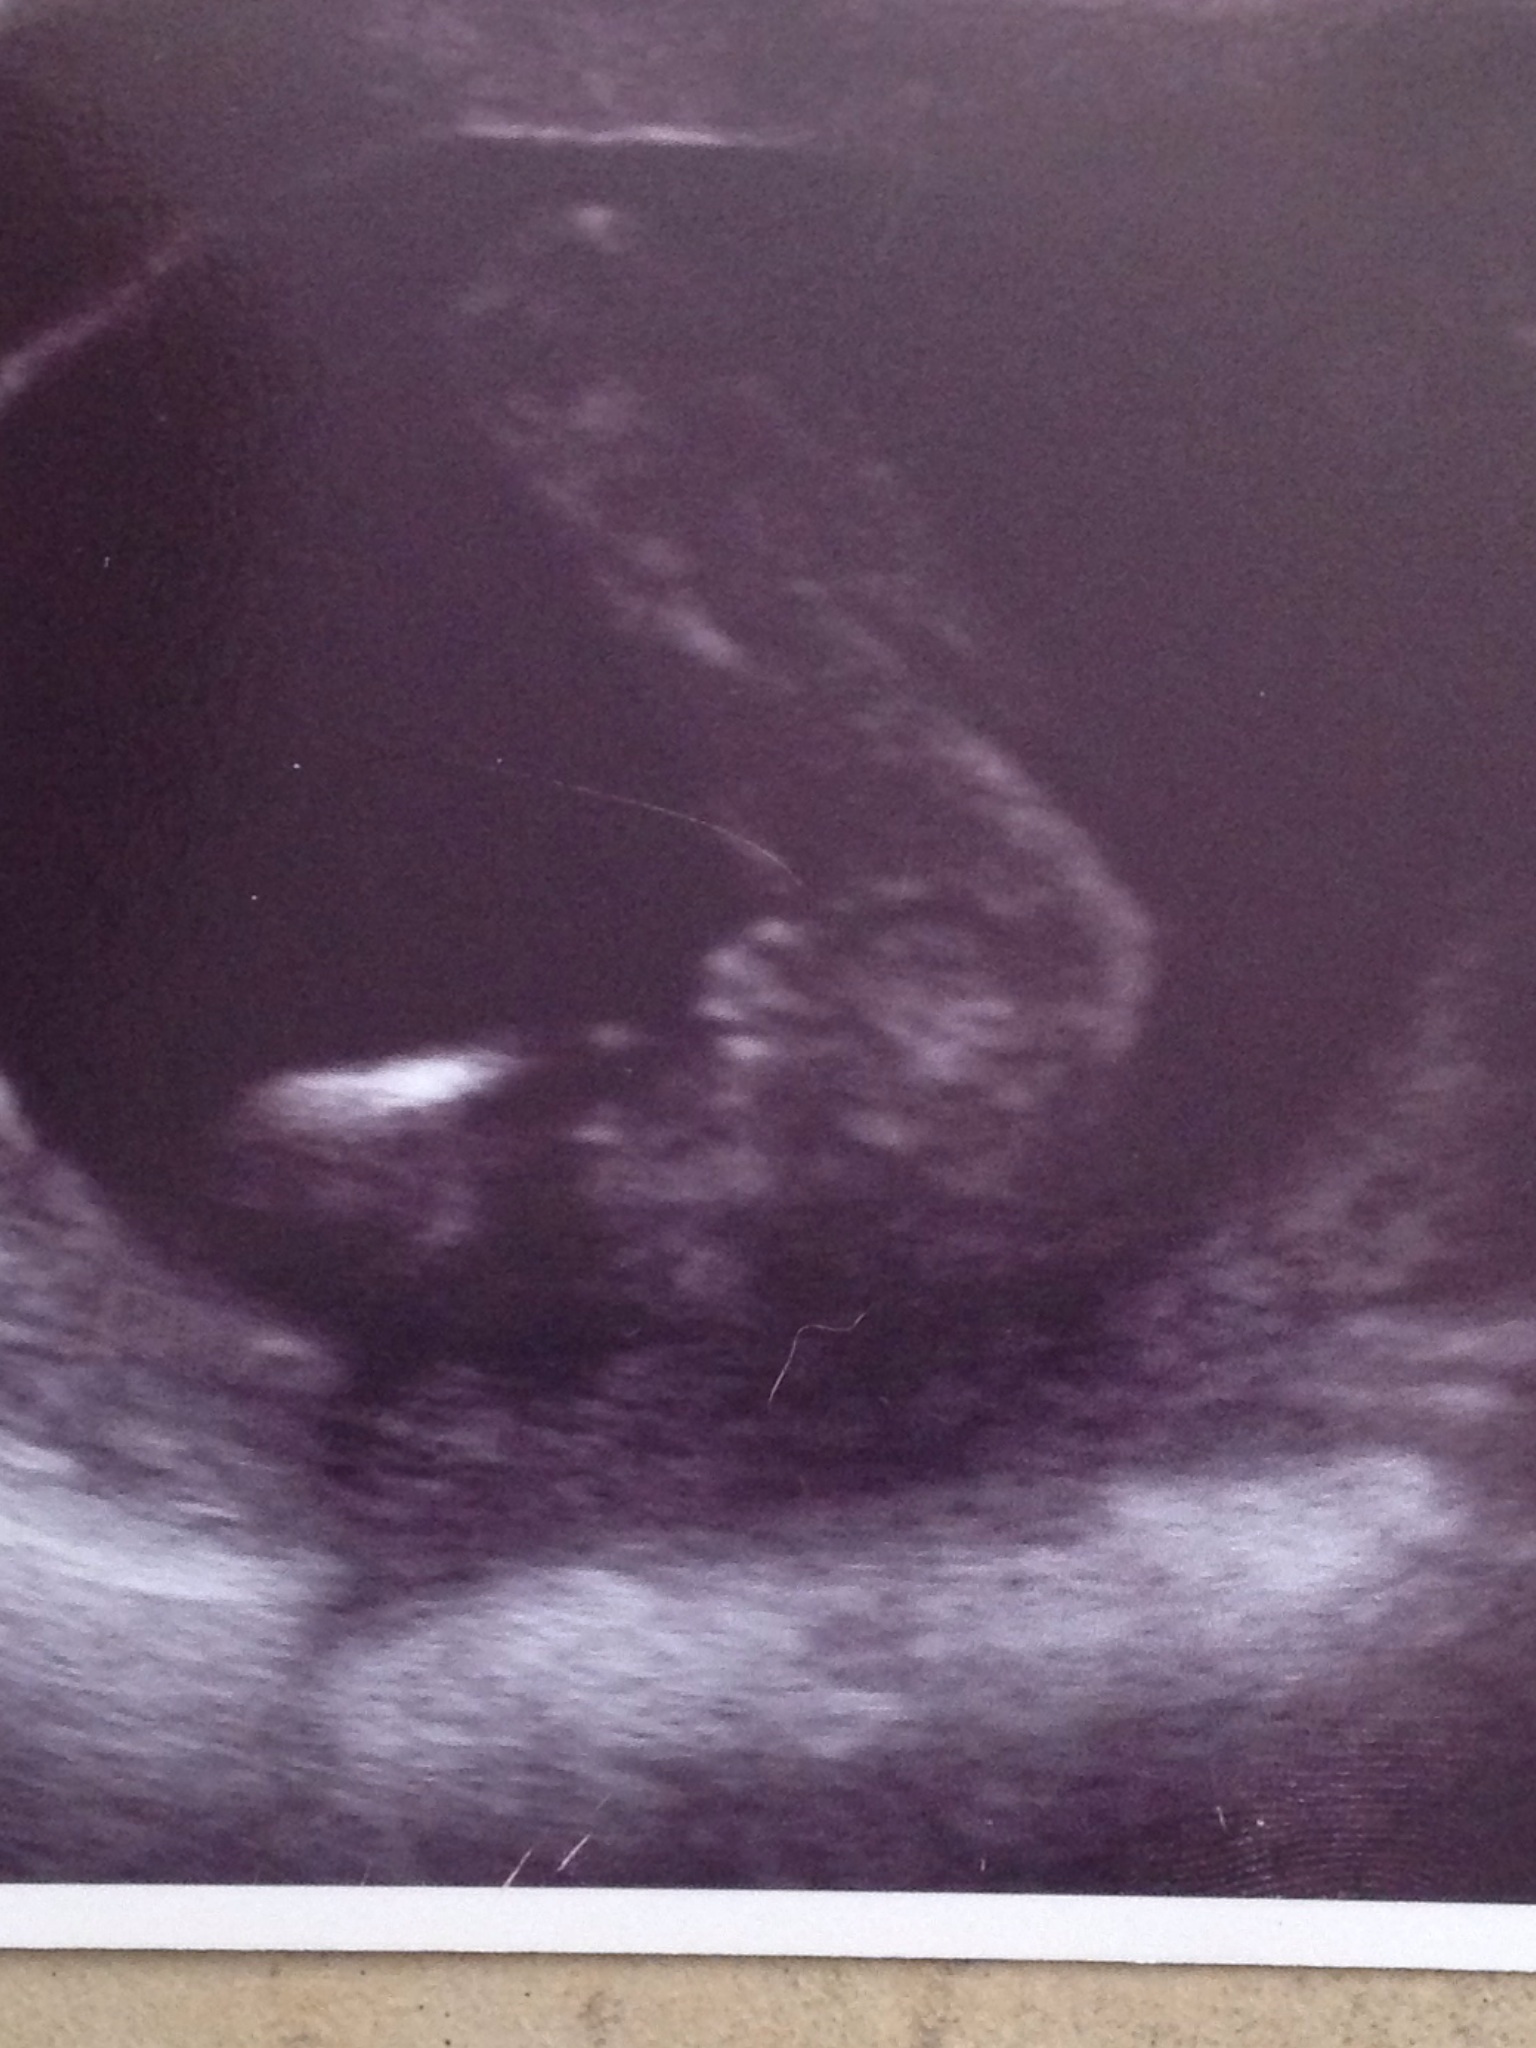

Please could you say girl or boy? I'm in disbelief!!!!Attachment 15166

100% girl!

Girl congrats x

All girl!!